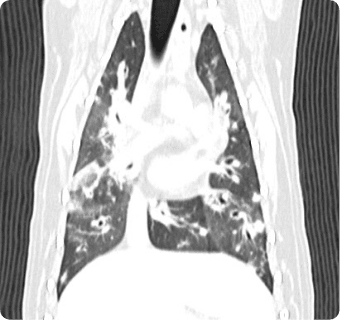

빠른 촬영속도를 통해 마취시간을 최소화 하며, 선명한 3차원 영상을 구현합니다.

종양, 전이평가, 선천적 혈관 기형 등 여러 질환의 조기 발견 및 환자상태를 평가합니다.

폐 실질 평가, 폐 염전, 폐 종양, 종격동 종양, 심장종양, 폐 전이 평가, 기관, 기관지, 식도의 평가, 복막심낭횡격막탈장, 동맥관개존증